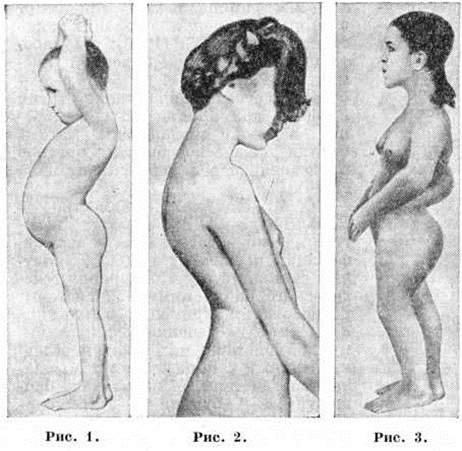

ЛордозЛордоз (lordosis; греческий lordos согнувшийся, сутулый + -osis) — искривление позвоночника, выпуклостью обращённое кпереди. Позвоночник взрослого человека имеет физиологический изгибы: в шейном и поясничном отделах кпереди — шейный и поясничный Лордоз, в грудном и крестцовом отделе кзади — грудной и крестцовый кифоз (смотри полный свод знаний), в силу чего его профильный контур образует волнообразную линию. Физиологический шейный Лордоз формируется у ребёнка на первом году постэмбрионального развития, что связано с активным удержанием головы в вертикальном положении; он захватывает все шейные позвонки и два верхних грудных, а его вершина приходится на V—VI шейные позвонки. Поясничный Лордоз формируется у ребёнка с появлением функции прямостояния и ходьбы; он захватывает все поясничные, XI и XII грудные позвонки, а его вершина соответствует III — IV поясничным позвонкам. Патологический Лордоз может быть результатом увеличения (гиперлордоз) или уменьшения степени физиологический Лордоз или сформироваться на уровне физиологический кифоза. Как самостоятельное заболевание патологический Лордоз почти не встречается, как вторичная компенсаторная деформация (компенсаторный Лордоз) наблюдается часто. Кроме того, различают приобретённый Лордоз, возникающий при различных заболеваниях и деформациях опорно-двигательного аппарата, и врождённый Лордоз, образующийся на уровне аномалий развития тел позвонков (смотри полный свод знаний Позвоночник). Возникновение компенсаторного поясничного гиперлордоза объясняется тем, что позвоночник, таз и нижние конечности с тазобедренными суставами представляют единую систему опоры и движения. Изменение в одном из её звеньев неизбежно приводит к изменениям во всей системе. Наиболее часто поясничный гипер лордоз формируется как компенсаторный при наличии сгибательной контрактуры тазобедренного сустава, например, при врождённом вывихе бедра (рисунок 1) или его анкилозе в положении сгибания при инфекционные (в том числе туберкулёзном) коксите, при деформирующем коксартрозе, у лиц, перенёсших полиомиелит с поражением мышц нижних конечностей и таза и церебральный спастический парез нижних конечностей, при системных заболеваниях костей и суставов и другие Поясничный компенсаторный гиперлордоз у этих больных образуется в связи с наклоном таза и следующих за ним поясничных позвонков кпереди. Он является сажным приспособительным механизмом, обеспечивающим в патологический условиях вертикальную ось тела и расположение центра тяжести в области площади опоры. Вторичный компенсаторный гиперлордоз у детей и подростков остаётся мобильным, но при длительном существовании у взрослых он становится фиксированным и может стать причиной ограничения наклона корпуса кпереди и вторичных болезненных явлений, вызванных остеохондрозом (смотри полный свод знаний), дистрофическими изменениями в межпозвоночных сочленениях (смотри полный свод знаний Дискоз) и в области сближенных остистых отростков. Несколько иной механизм образования Тяжёлая гиперлордоза при врождённом и юношеском кифозе (рисунок 2), у детей с ахондроплазией (рисунок 3), спондилоэпифизарной дисплазией, эпифизарным дизостозом, холестеатомой, спастическим церебральным параличом, торсионным спазмом и полиомиелитом. В этих случаях причина развития гиперлордоза заложена в самом позвоночнике или мышцах, ведающих его функцией. При врождённом или юношеском кифозе, у детей с ахондроплазией, спондилоэпифизарной дисплазией, эпифизарным дизостозом патологический кифоз в нижних грудных и верхних поясничных позвонках формируется на уровне клиновидно изменённых тел позвонков и суженных дисков. Ниже кифоза компенсаторно тела позвонков смещаются кпереди, что является причиной гиперлордоза. При спондилолистезе гиперлордоз образуется вследствие смещения кпереди V поясничного позвонка. При спастическом церебральном параличе и торсионном спазме, а также при оболочечно-корешковом синдроме, связанном с холестеатомой, гиперлордоз развивается вследствие напряжения мышц спины. Шейный гиперлордоз возникает у детей с посттравматическим синостозом в заднем отделе позвоночника (при разрыве межостистой и жёлтой связок). У детей, перенёсших полиомиелит, при глубоком парезе мышц передней брюшной стенки и сохранной функции длинных мышц спины также формируется патологический гиперлордоз. |